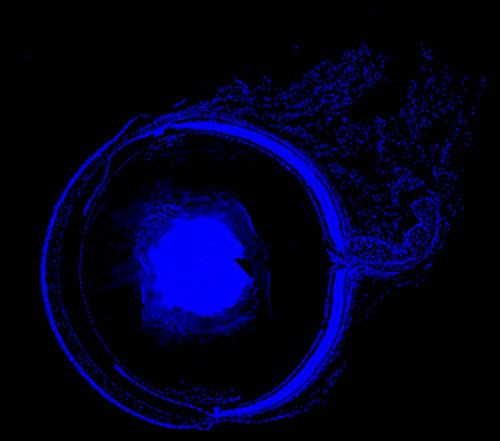

DAPI染色-小鼠眼球